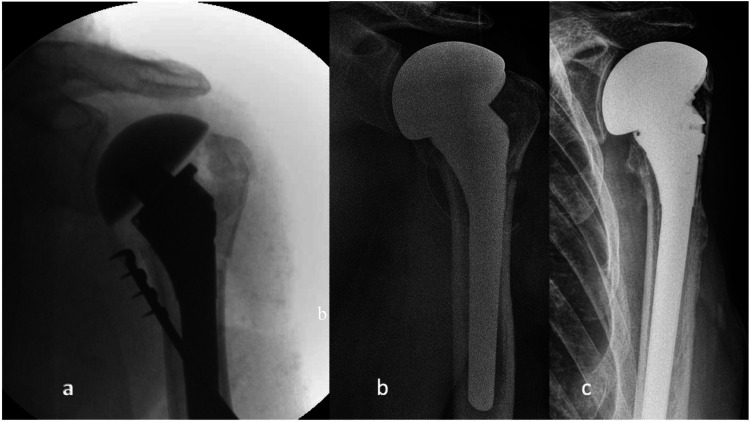

Introduction: Anatomic hemiarthroplasty (aHA) is a treatment option for non-reconstructable constructable multifragment proximal humeral fractures that preserves range of motion. Our study aims to evaluate the radiographic and clinical outcomes of patients who received a modular aHA with anatomical sizing of the tubercle-bearing metaphyseal components.

Materials and methods: The medical records of thirty-nine consecutive patients were reviewed. Patients were treated at a single institution with aHA as first-line treatment following a non-reconstructable constructable proximal humeral fracture. Tubercle resorption and cranialization of the aHA were analyzed using radiographic controls. Patient clinical function was assessed using the Constant Murley Score (CS).

Results: Twenty-four patients (62%) were available for clinical follow-up, with a mean CS of 54 points after a mean 56-month follow-up period. There was no significant difference in functional outcome on average between patients with healed tubercles (CS = 57) and resorbed tubercles (CS = 51). Radiographic follow-up was available in 33 patients (85%), demonstrating healed tubercles in 33% of the patients. Patients with resorbed tubercles had significant smaller acromio-humeral distances (AHD) than patients with healed tubercles (p = 0.043). A positive correlation was observed between greater AHD and increased constant scores (p = 0.022).

Conclusions: The final patient outcome measures demonstrated a positive correlation with a greater acromio-humeral distance and tubercle healing rates. However, the modular stem design with sizing of the metaphyseal components did not result in superior outcomes when compared with the literature.